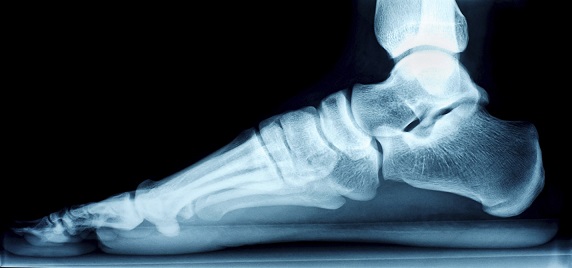

در معاينه٬ چه در موقع خوابـيده و نشسـته و چـه در حـالت ايستاده ٬ قوس کف پايي وجـود نـدارد و پـا در حـالت والگـوس است. حـرکات مـفصل مـچ پـا غـالبا طـبيعي است ولي حـرکات مفصل زير مچ بخصوص چرخش به داخـل مـحدود و بـا درد و انقباض عضلات نازک ني همراه است . اين بيماران ا کثرا دچار پيچ خوردن مکـرر مـچ پـا مـي شود. پـرتونگاري مـچ پـا کـه بـايد در وضعيت مايل گرفته شود وجود پل استخواني بين اسـتخوان ها را نشان مي دهد (گاه اين پل غضروفي است و هنوز استخواني نشده است که در اين صورت در پرتونگاري مشهود نيست).

عـــلت ايــن بــيماري ٬ وجــود اتــصال (Coalition) بــين استخوان هاي مچ پـاست کـه عـموماً بـين اسـتخوان هاي تـالوس و کالکانئوس و يا تالوس و ناويکولر مي باشد .

بيماري غالباً در نوجوانان 12 تا 16 ساله ديده مي شود و معمول دوطرفه است . شـيوع در پسـران دوبـرابـر دخـتران است . در ايـن بيماري که غالباً بـا درد هـمراه است عـضلات نـازک ني مـنقبض هستند و پا را به طرف خارج مي چرخانند(والگوس).